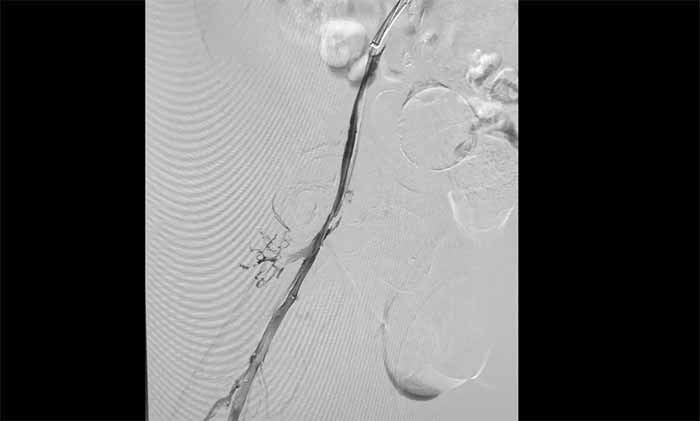

近日,上海藍(lán)十字腦科醫(yī)院腦血管病科收治了一名腦出血術(shù)后長(zhǎng)期臥床導(dǎo)致下肢深靜脈血栓形成的老年男性患者;颊咴谕庠嚎祻(fù)期間發(fā)現(xiàn)右下肢嚴(yán)重腫脹,超聲提示深靜脈血栓,緊急轉(zhuǎn)入本院。

席剛明教授與腦血管病一科4A病區(qū)副主任王貴平博士分析指出,下肢深靜脈血栓一旦脫落,可隨血流引發(fā)肺栓塞,危及生命?紤]到患者血栓形成時(shí)間較長(zhǎng)、抗凝效果不佳,團(tuán)隊(duì)決定行介入手術(shù)治療。術(shù)后造影顯示血栓基本消失,下肢靜脈恢復(fù)通暢,患者右下肢腫脹明顯緩解。

▲ 取出大量血栓